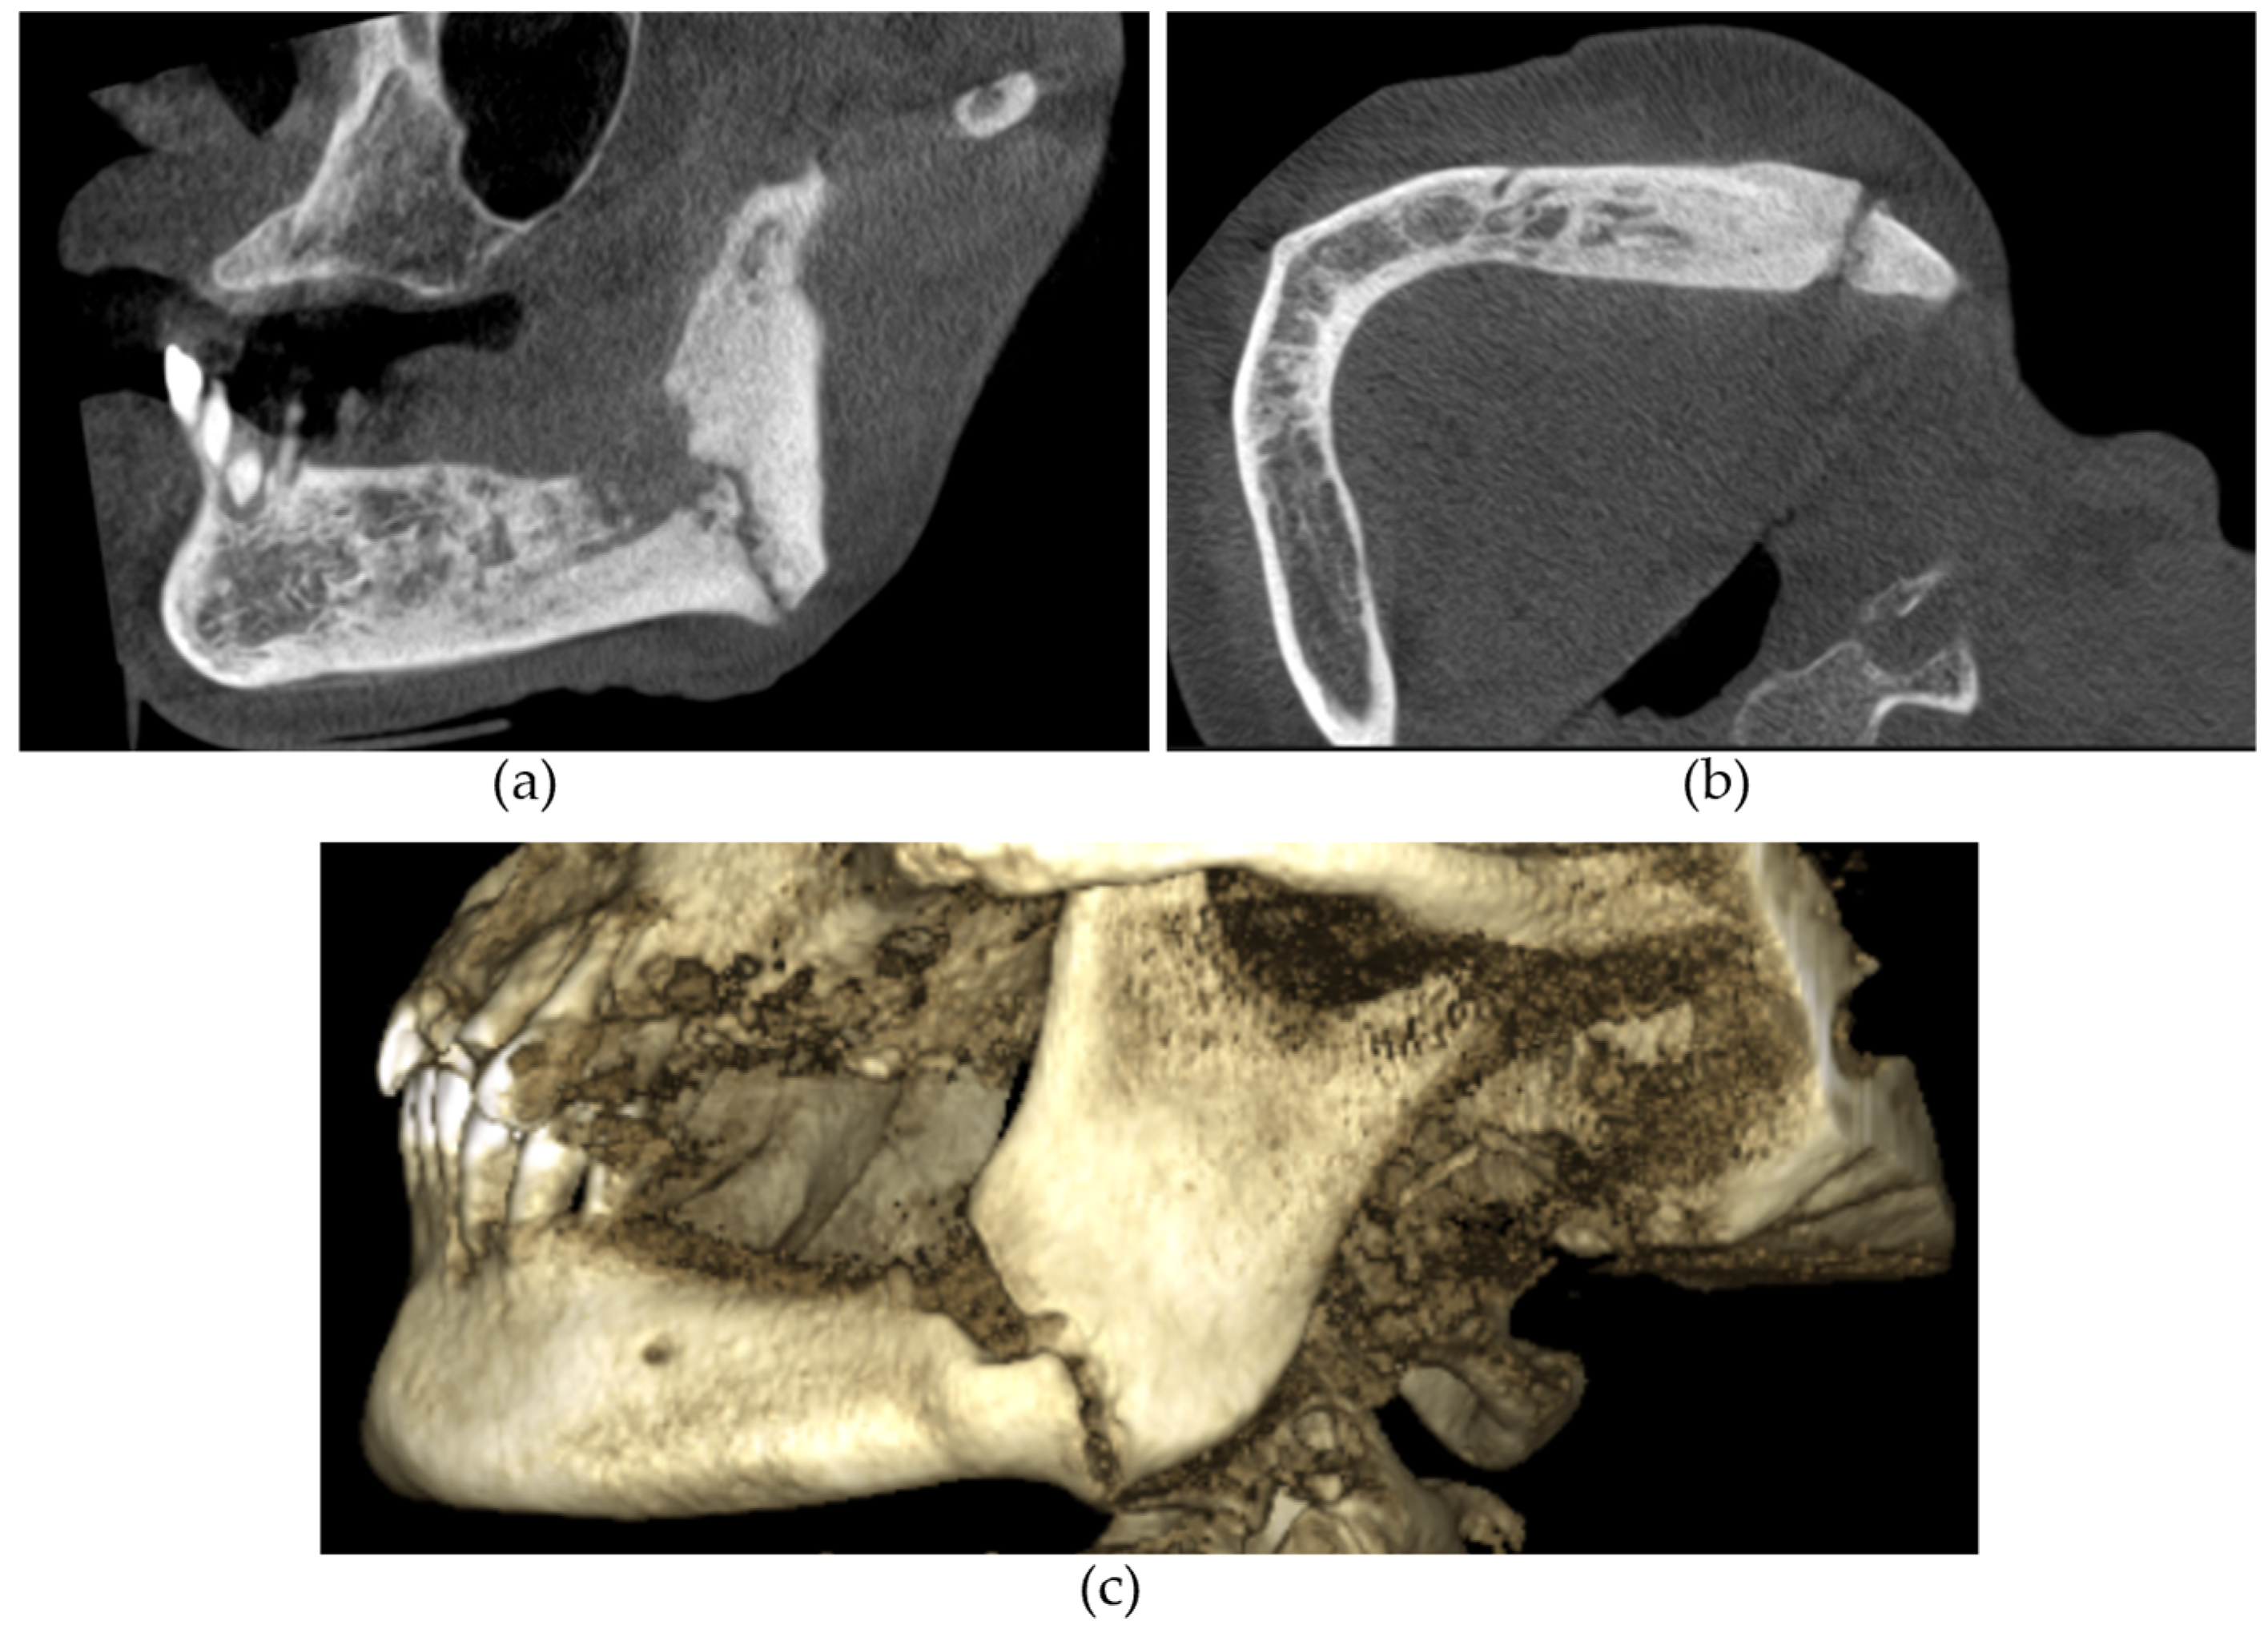

The CBCT findings commonly observed in patients with MRONJ are osteosclerosis, osteolysis, periosteal reaction, and sequestration [13,14,15,16,17,18]. The histomorphological analyses of MRONJ lesions have revealed three distinct patterns: (1) prominent bone resorption in regions of active inflammation, (2) acellular necrotic sequestra with large Haversian canals, and (3) increased inter-osteonic bone deposition with smaller Haversian canals and trabecular thicknesses in non-necrotic regions [19]. Abnormal bone remodellling characterised by reduced osteoclastic activity and increased appositional osteogenesis contributes to the radiological pattern observed in MRONJ lesions. In earlier stages of MRONJ, non-healing extraction sockets, the thickening of lamina dura, and periodontal ligament (PDL) space widening may also be observed [14,16,18,20]. In maxillary MRONJ, more prominent maxillary sinus mucosal thickening can be observed, although no significant differences in sinus volumes have been noted [21]. These radiological manifestations are illustrated in Figure 1, Figure 2, Figure 3, Figure 4 and Figure 5.

Figure 1. (a) Sagittal and (b) axial sections demonstrating an osteolytic lesion with sequestrations in the left mandible. Arrows demonstrate the sequestrations.